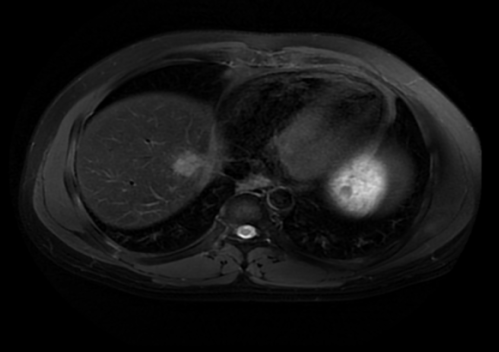

2022.09.21肝脏放疗结束后复查肝脏MRI:肝VIII段转移灶治疗后改变,病灶基本消失。

“医生们定期进行肝脏磁共振检查,结果显示肿瘤逐渐缩小,如同拨云见日。”邱素芳主任介绍,鼻咽癌治疗一定要边观察边调整,根据病人的实际情况和疗效来调整治疗方案及强度、在综合治疗的同时,又要具有个体化特点。

当放疗结束后程先生再进行复查时,喜讯传来——肿瘤完全缓解,已经在影像学上消失不见了,程先生一家开心不已。